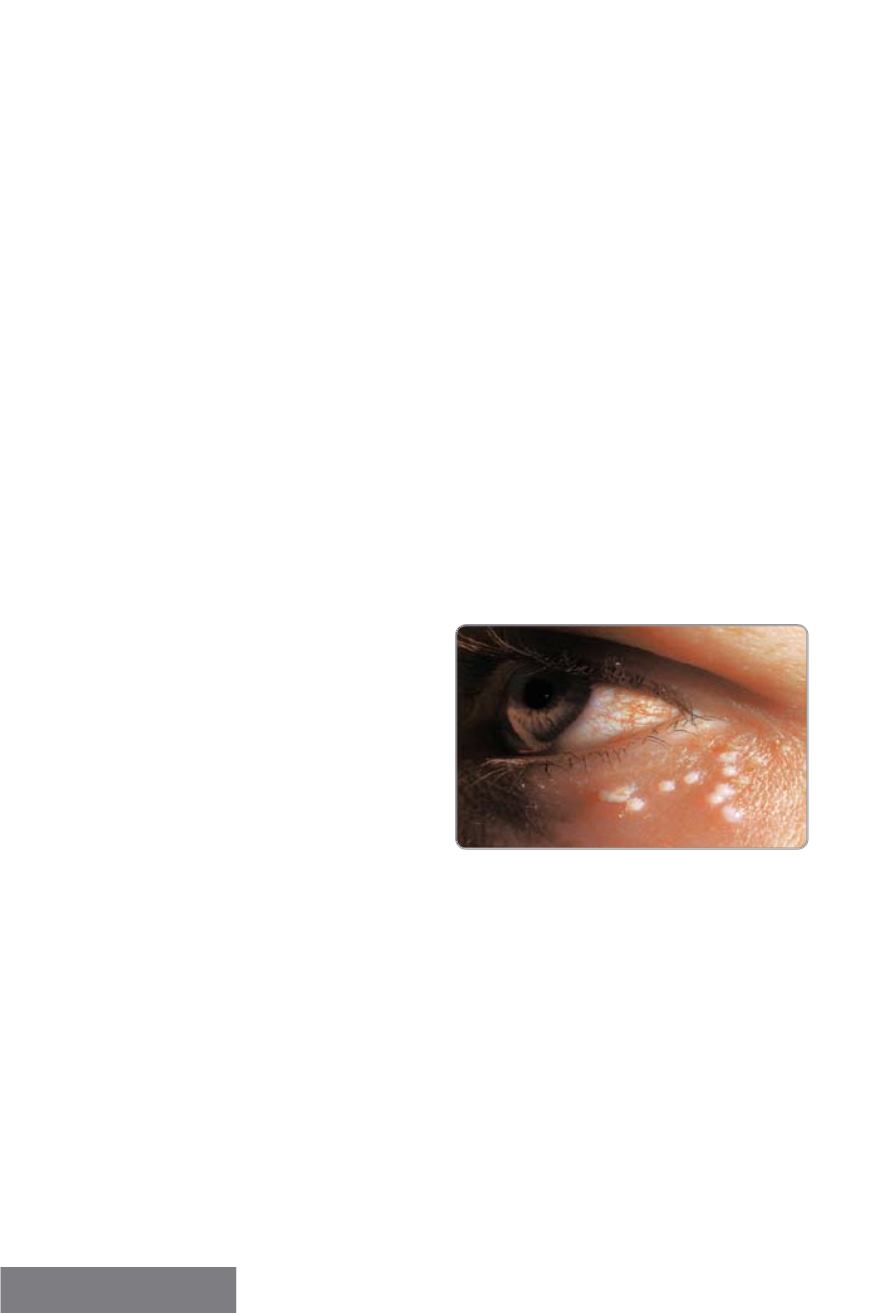

Blefaroconjuntivitis

folicular unilateral

Se presenta con adenopatía preauricular y

vesículas palpebrales.

Este tipo de conjuntivitis con lesiones en

los párpados es la forma más común de

recurrencia por HSV representando el 83%

de las recurrencias

(Fig.4).